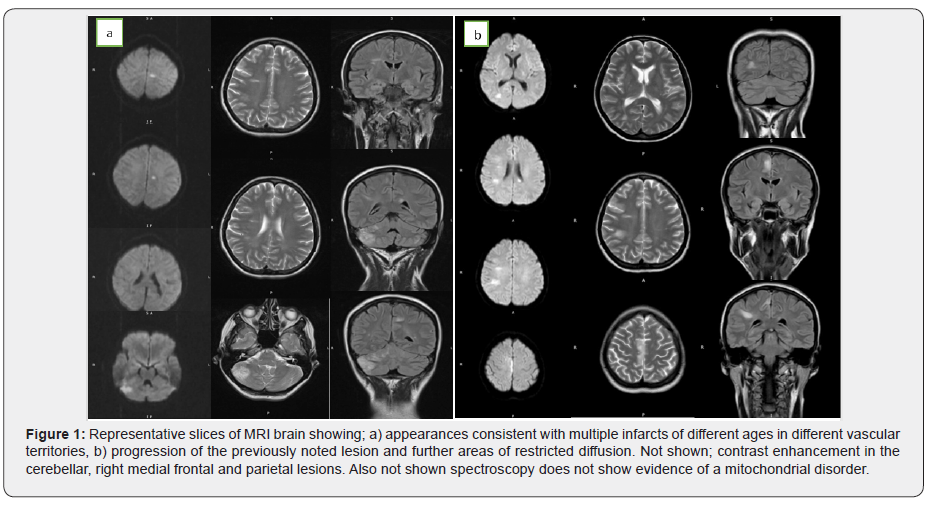

A subsequent MRI head demonstrated multiple areas of restricted diffusion in different vascular territories (Figure 1a). There were also foci of high T2 signal changes in the supra-tentorial white matter, with some demonstrating restricted diffusion. Considering the different territories, and different ages of these lesions, a cardio-embolic source was the most likely cause of these infarcts. Her trans-thoracic echocardiogram (TTE) was normal, as was her carotid Doppler. A lumbar puncture showed normal CSF. At this point she developed episodes of seizures corroborated by EEG.

Two weeks after this, she started to deteriorate. Her seizures became more frequent and her dysphasia more pronounced. A repeat MRI brain (Figure 1b) showed an increase in size of the lesions in the medial frontal and parietal lobes. New lesions in the corpus callosum and left thalamus showed restricted diffusion. The cerebellar, right medial frontal and parietal lesions enhanced with contrast. Long- and short-term MRI head spectroscopy did not show any evidence of a lactate peak to suggest mitochondrial disorder. This picture was consistent with a diagnosis of vasculitis.